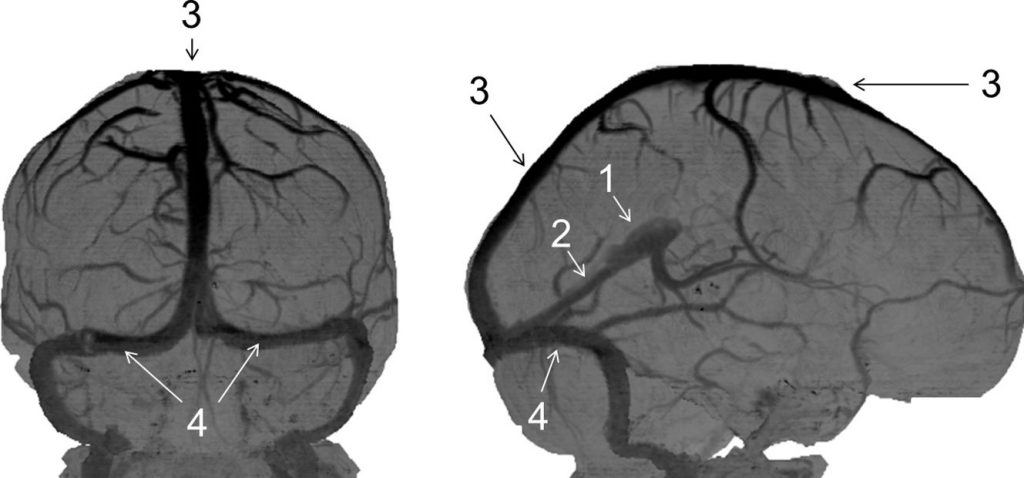

Fig. 48.2 Veines de l’encéphale (angioscanner).

1. Grande veine cérébrale (de Galien) (système veineux profond). 2. Sinus droit. 3. Sinus sagittal supérieur. 4. Sinus latéraux.